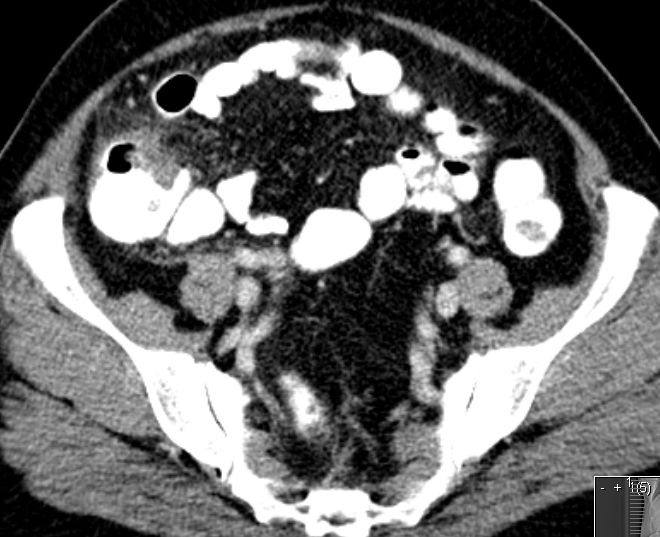

91-jährige Frau 2 Jahre nach OP einer muzinösen Neoplasie der Appendix. Jetzt Rezidiv.![]() |

![]() |